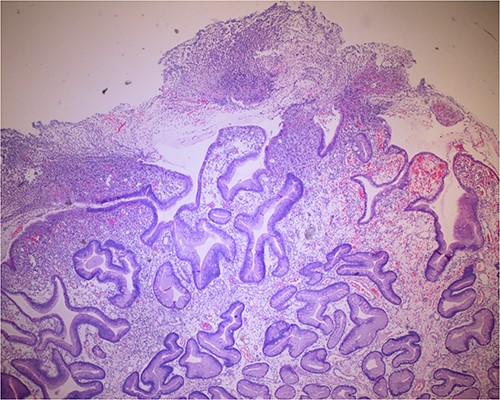

Histologic sections of the polyps demonstrated benign gastric hyperplastic polyps with acute and chronic gastritis (Fig. 2). Portions of the gastric polyps and adjacent mucosa were covered by inflammatory cell exudate (Fig. 3). Higher magnification revealed conspicuous volcanic-like eruption of the exudate, reminiscent of pseudomembranous gastritis (Fig. 4). Alcian yellow and GMS stains were negative for Helicobacter pylori and fungal organisms, respectively.

Volcanic-like eruption of inflammatory exudate, reminiscent of pseudomembranous gastritis.